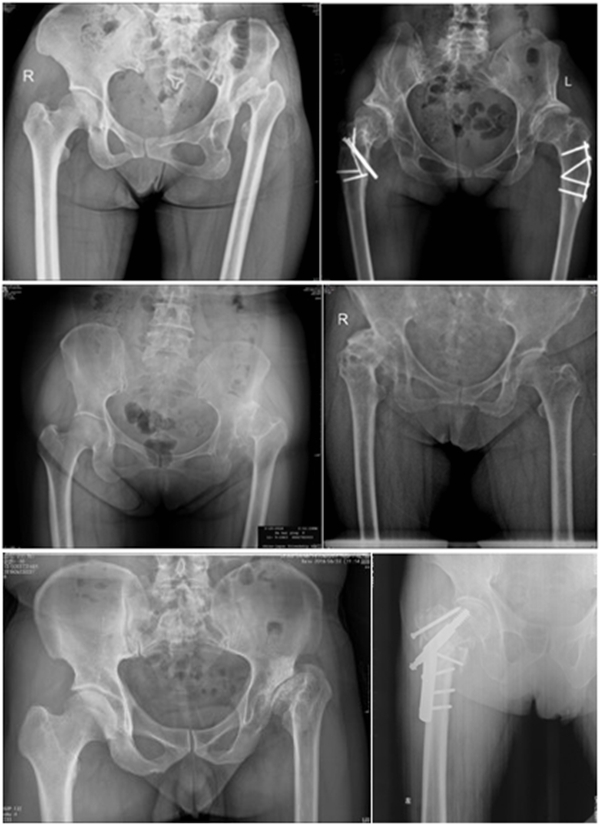

导致股骨近端畸形的原因主要有原发型和继发型两大类。原发型多为发育异常所致(DDH)、代谢性骨病、强直性脊柱炎引起;继发型主要为手术所致,包括股骨近端截骨术、股骨近端骨折内固定术、全髋或半髋置换,其他因素如感染、创伤畸形愈合等。

二、股骨近端畸形的分型---Berry分型

继发畸形多种多样,很少有病例与分型完全一致,但其核心要素是畸形位置和畸形类型。

畸形位置:大粗隆、股骨颈、干骺端、股骨干

畸形类型:成角畸形、旋转畸形、横行畸形、髓腔异常

Ⅲ、干骺端畸形

转子间骨折畸形愈合后常导致干骺端畸形,干骺端遗留大量硬化骨或髓腔成角,术中需在确认髓腔开口位置后,首选用小骨刀或高速磨钻去除硬化骨,打通髓腔。

干骺端畸形还可引起髓腔增宽,骨量减少,骨质疏松,不能为近端压配固定型的假体提供良好稳定。宜选用全微孔涂层远端固定假体。